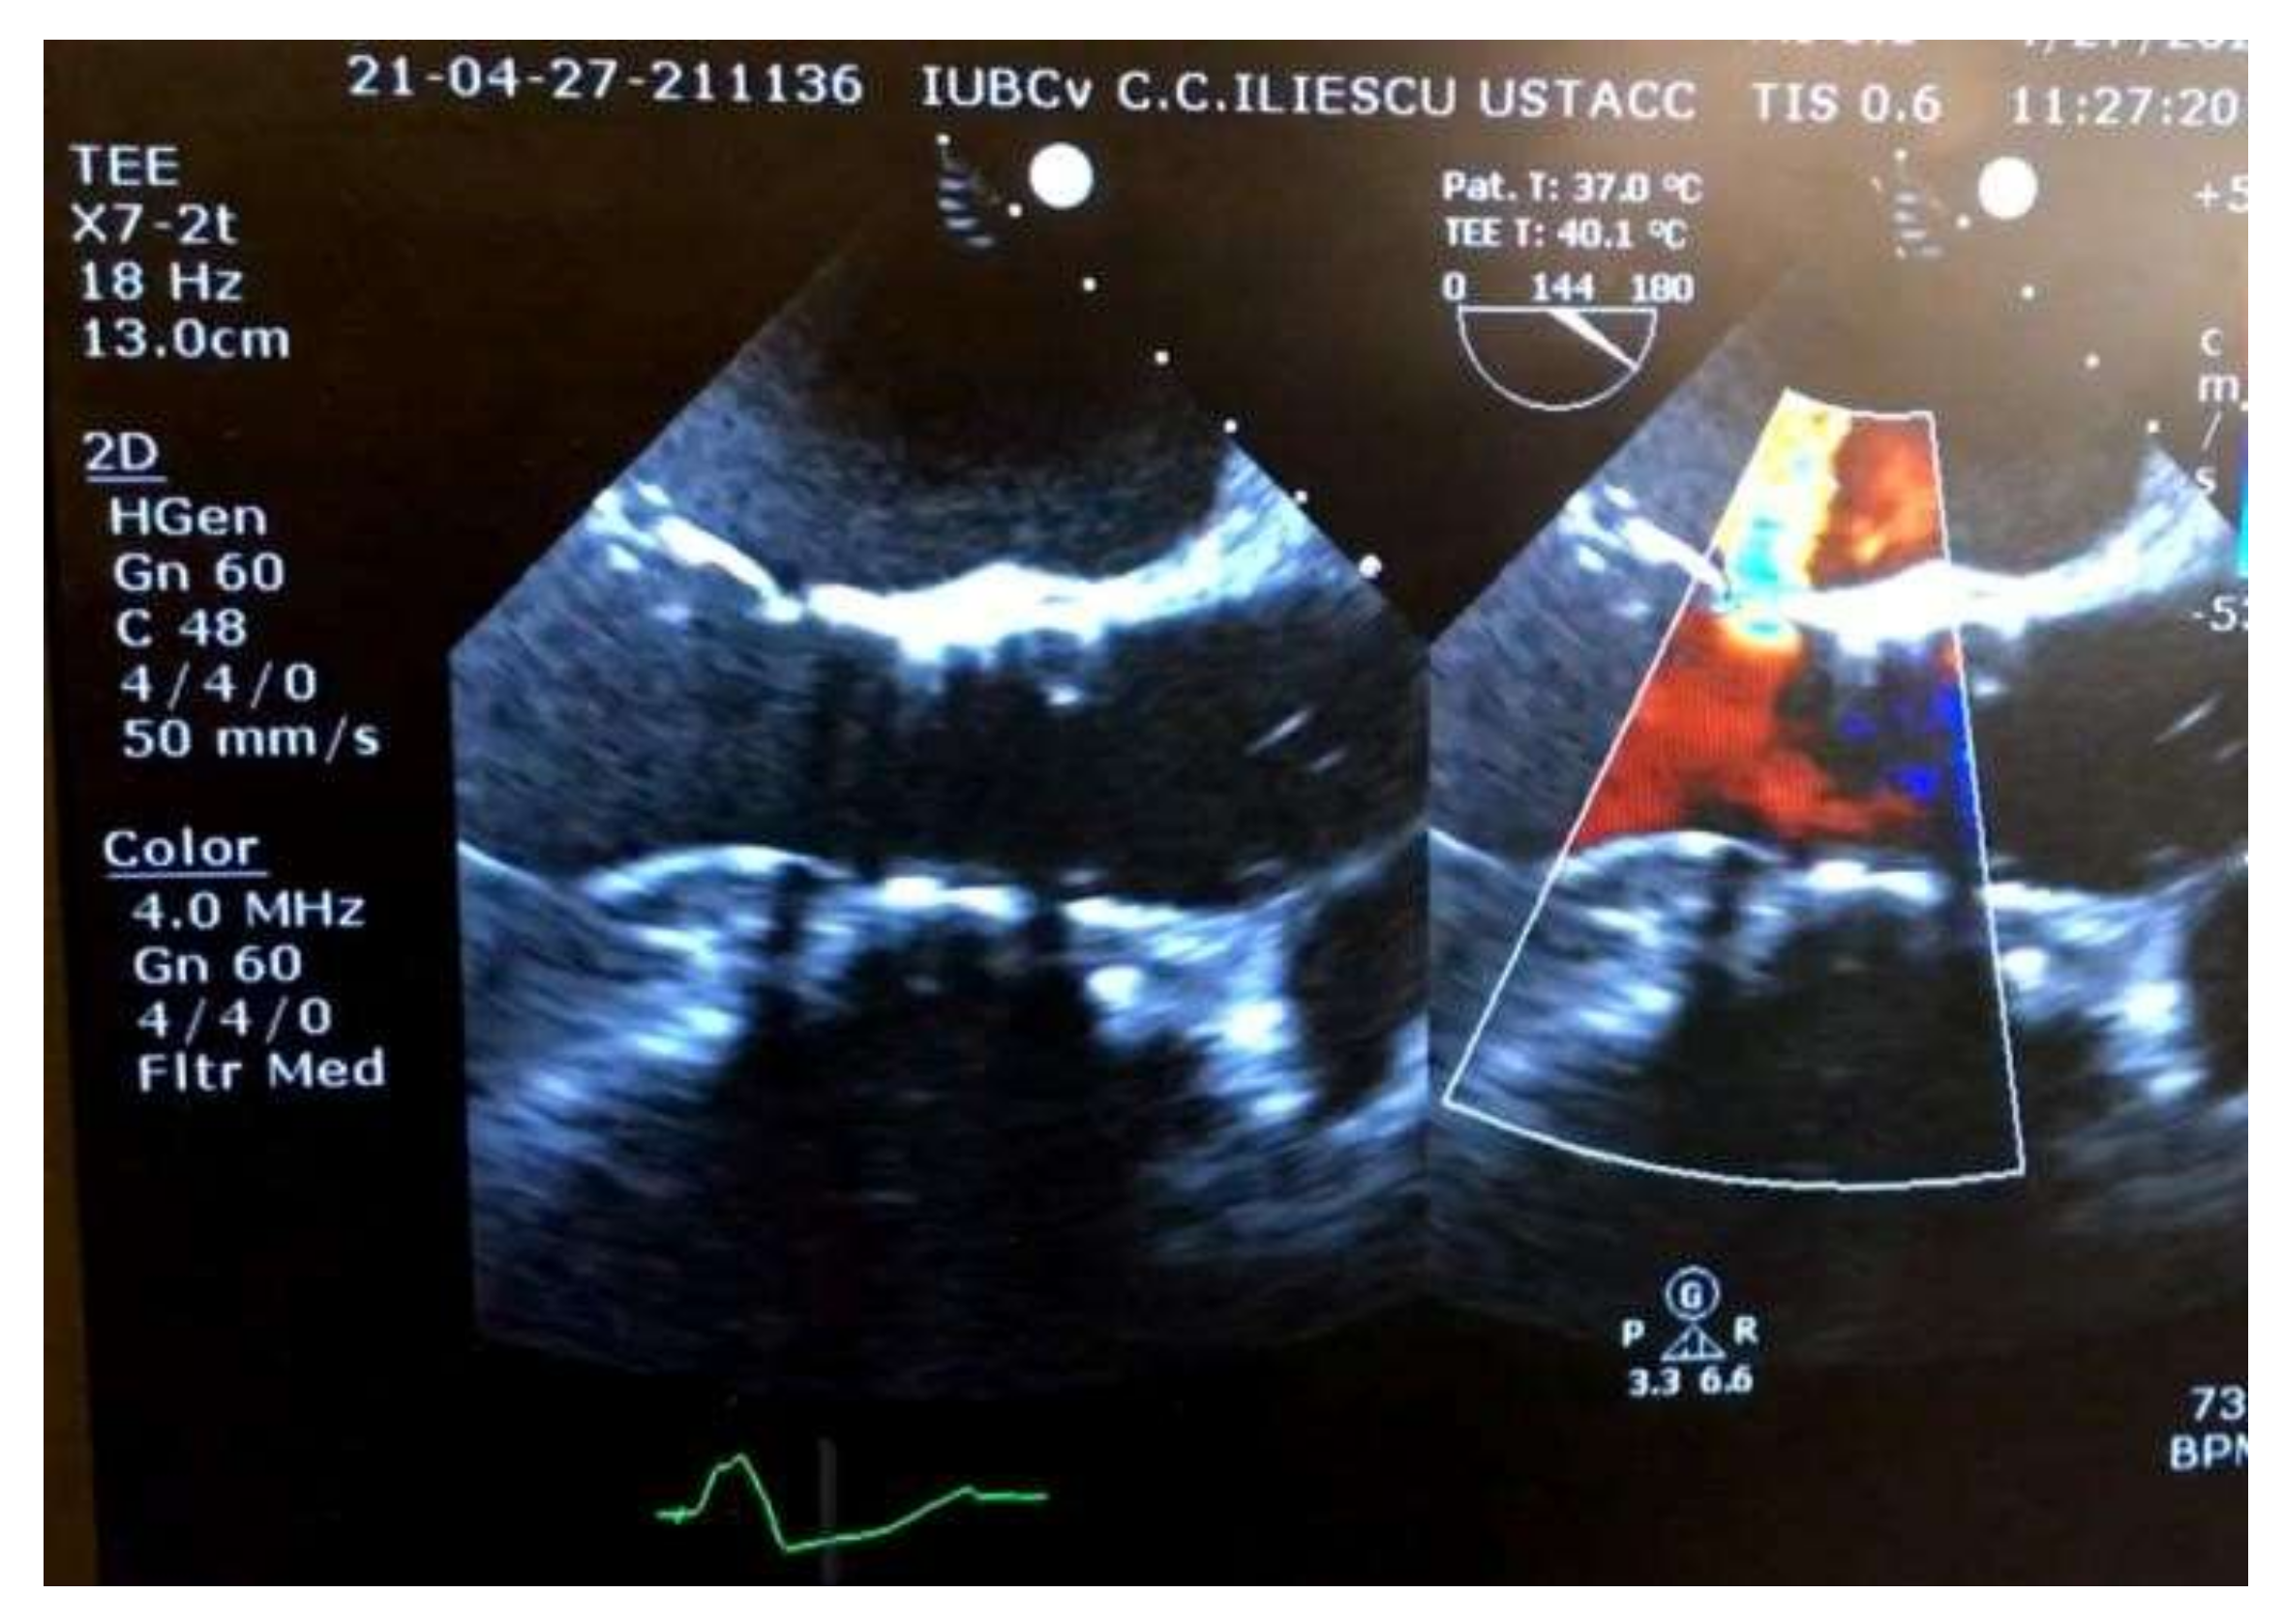

2. Case Report